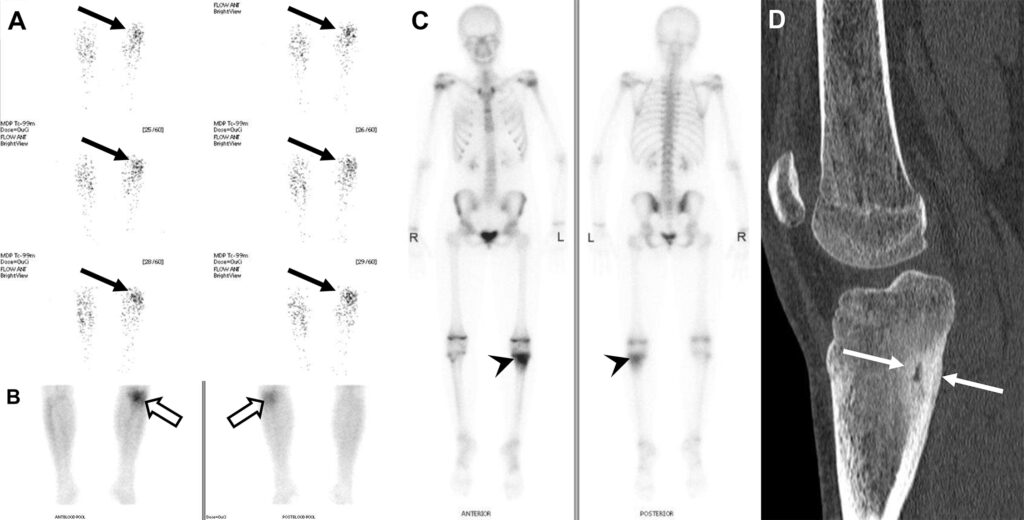

Osteoma osteoide in un adolescente di 15 anni con dolore all’arto inferiore sinistro, accentuato durante la notte.

La scintigrafia ossea trifasica risulta positiva in tutte e tre le fasi a livello della tibia prossimale sinistra. Si apprezza iperafflusso vascolare, iperemia locale e l’inconfondibile segno della “doppia densità” nelle acquisizioni tardive.

Il nidus tumorale centrale (radiotrasparente alla TC, altamente vascolarizzato e metabolicamente attivo) corrisponde al “cuore” di ipercaptazione focale molto intensa in scintigrafia. L’osso sclerotico reattivo circostante (visibile come ispessimento denso alla TC) corrisponde all’alone di captazione più sfumata (la seconda “densità”) che circonda il focus centrale in scintigrafia.